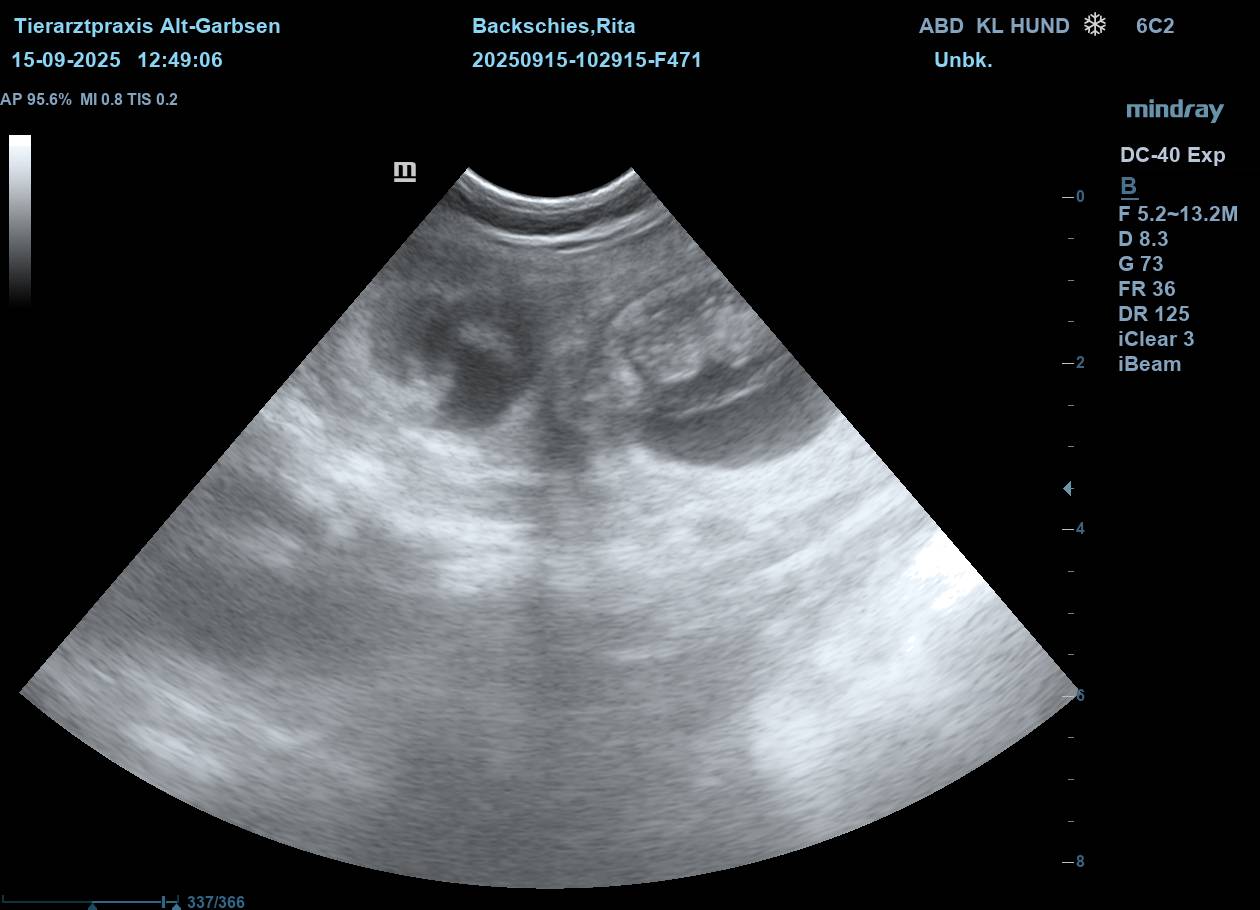

| Mo, 15.09.2025 | Es bahnt sich was an… der S-Wurf aus dem Zwinger Vom Lahberg FCI ist in die Produktion gegangen. Die Verpaarung am 17.08.2025 von Julissa Lisant Ingrid für Wambachtal „Rita“ und Kuddel vom Lahberg FCI war erfolgreich.🌿 Wir dürfen gespannt sein. In den nächsten Wochen werden wir dann Bilder vom wachsenden Babybauch posten. ![]() ![]() ![]() ![]() ![]() Jetzt heißt es mal wieder abwarten, beobachten, Däumchen drehen und hoffentlich bald freuen. |